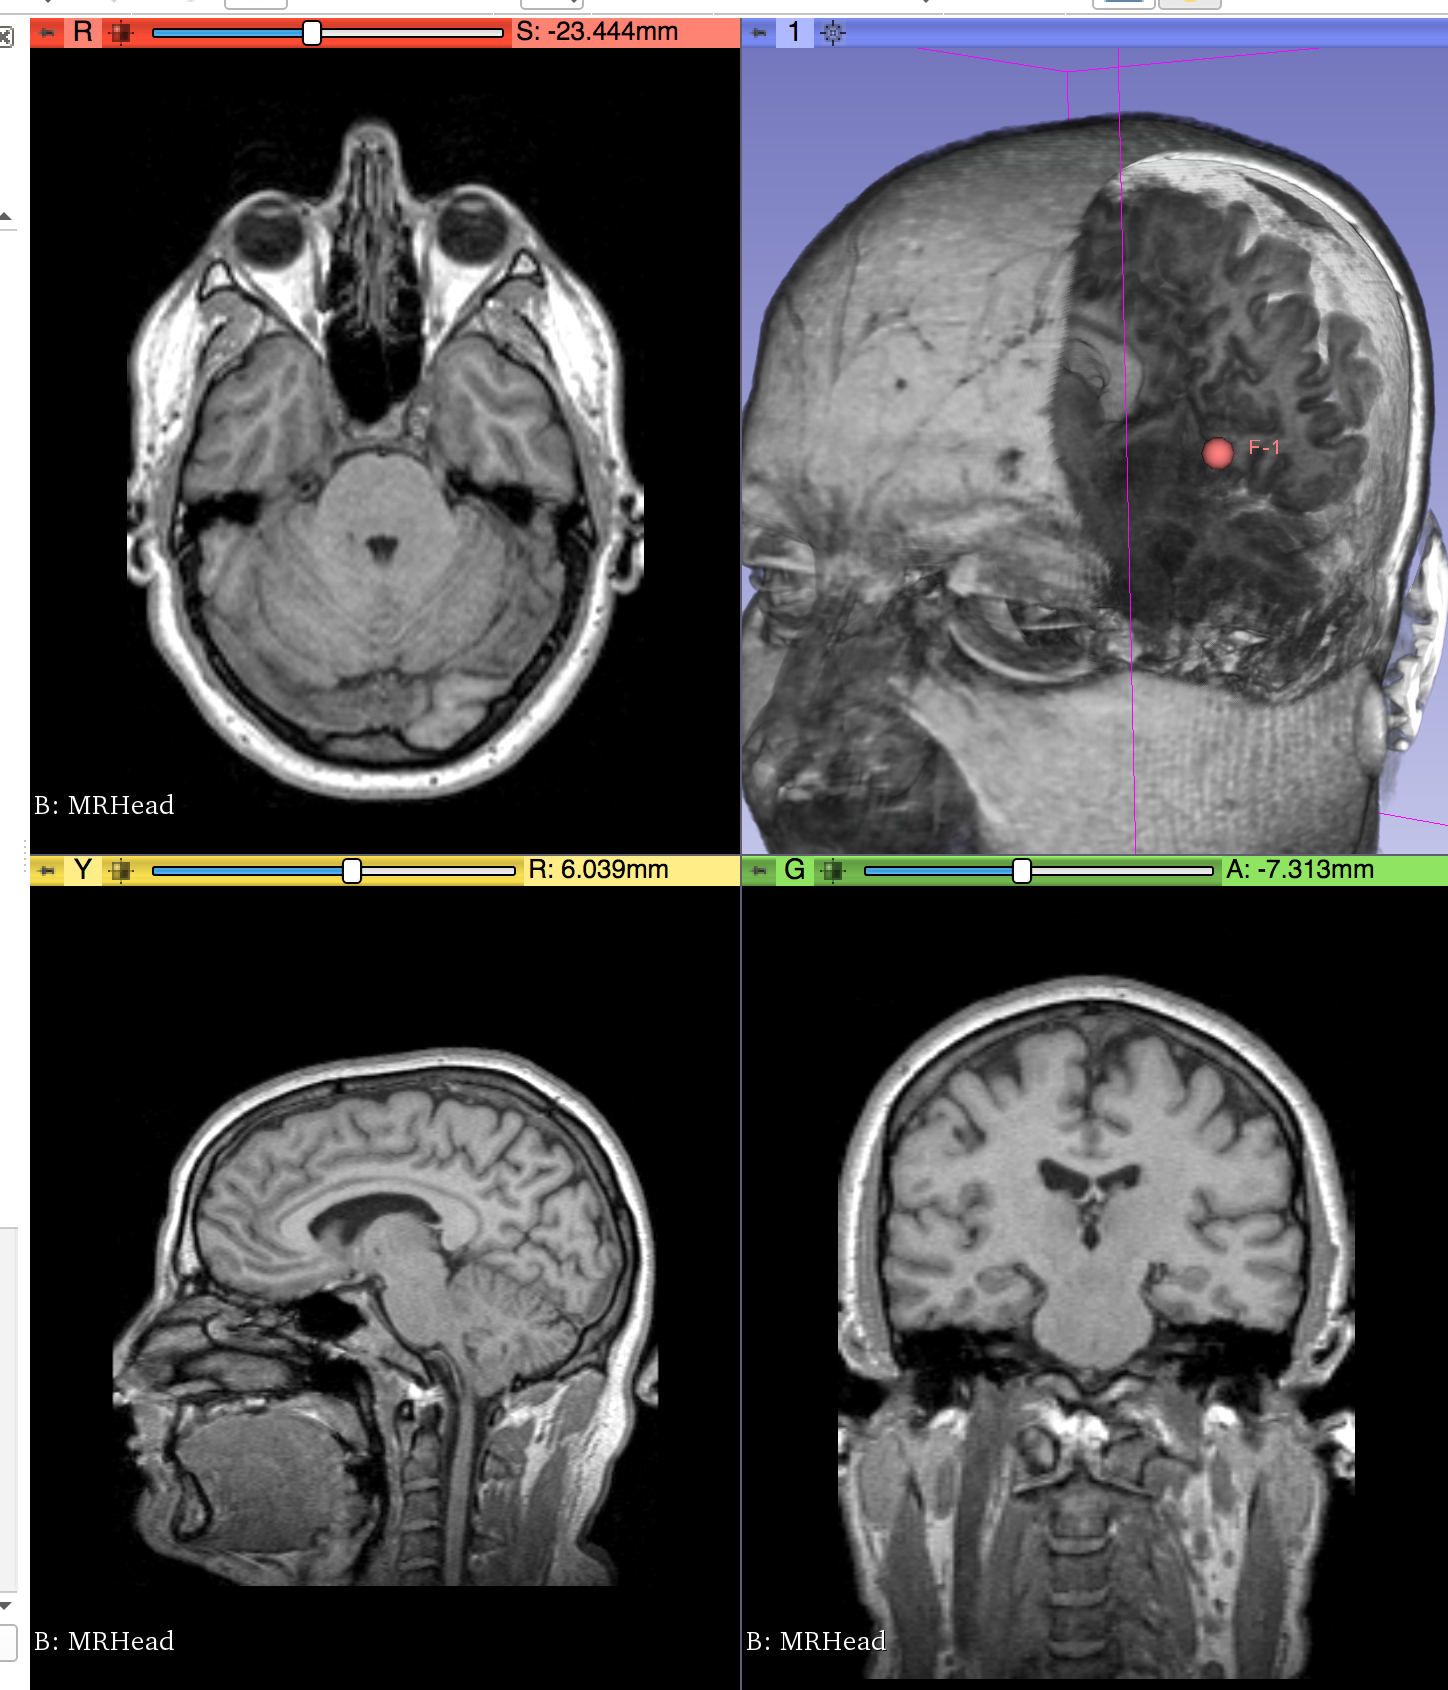

- Provided a proof of concept (python script) for dynamic shader editing in Slicer (see image, video and link to script below)

Proof of concept

Result

Illustrations

| Philips 3D US | Chroma-depth in PRISM | Depth peeling in PRISM |

|---|---|---|

|

|

|

| Edge enhancement in PRISM | Decluttering in PRISM | Volume carving in PRISM |

|---|---|---|

|

|

|

| Blood flow animation in PRISM | ||

|---|---|---|

|